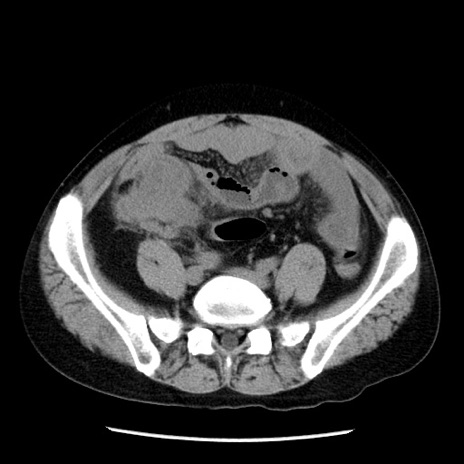

症例29(横断像)

【症例】40歳代男性

【現病歴】2日前から胃痛あり。徐々に周期的な激痛に変化した。本日になっても激痛があるため受診。

【身体所見】意識清明、BT 38-39℃台あり、腹部:膨満、やや硬、右下腹部に圧痛あり。

【データ】WBC 8500、CRP 23.26